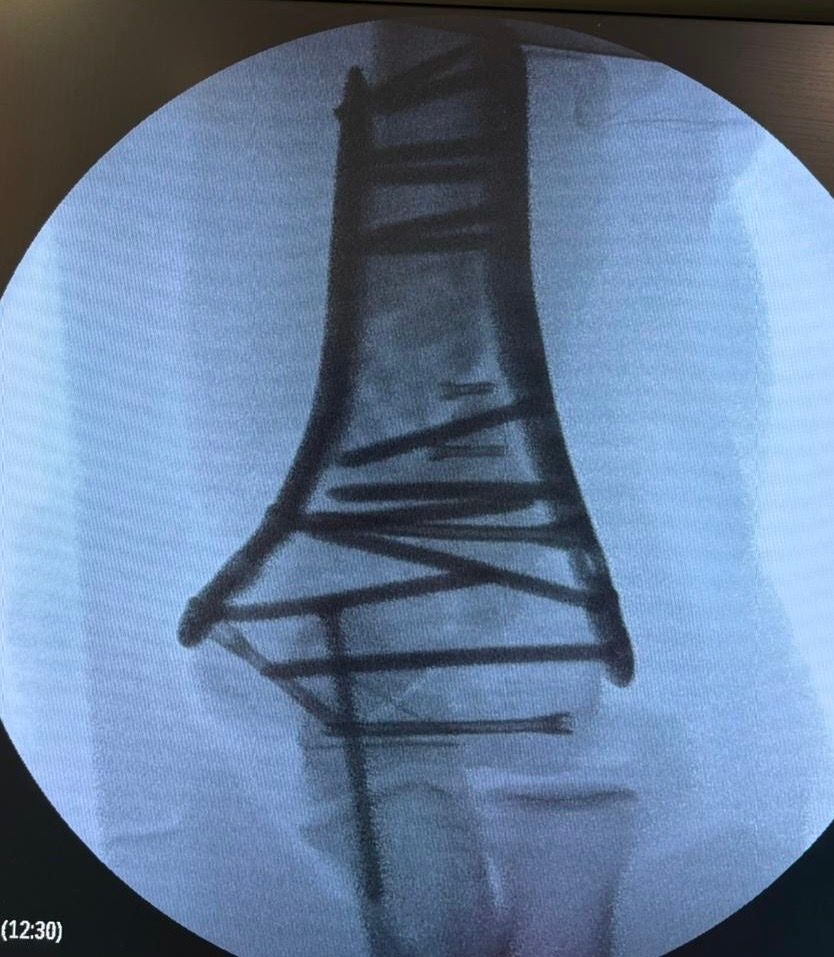

Fotos y vídeos